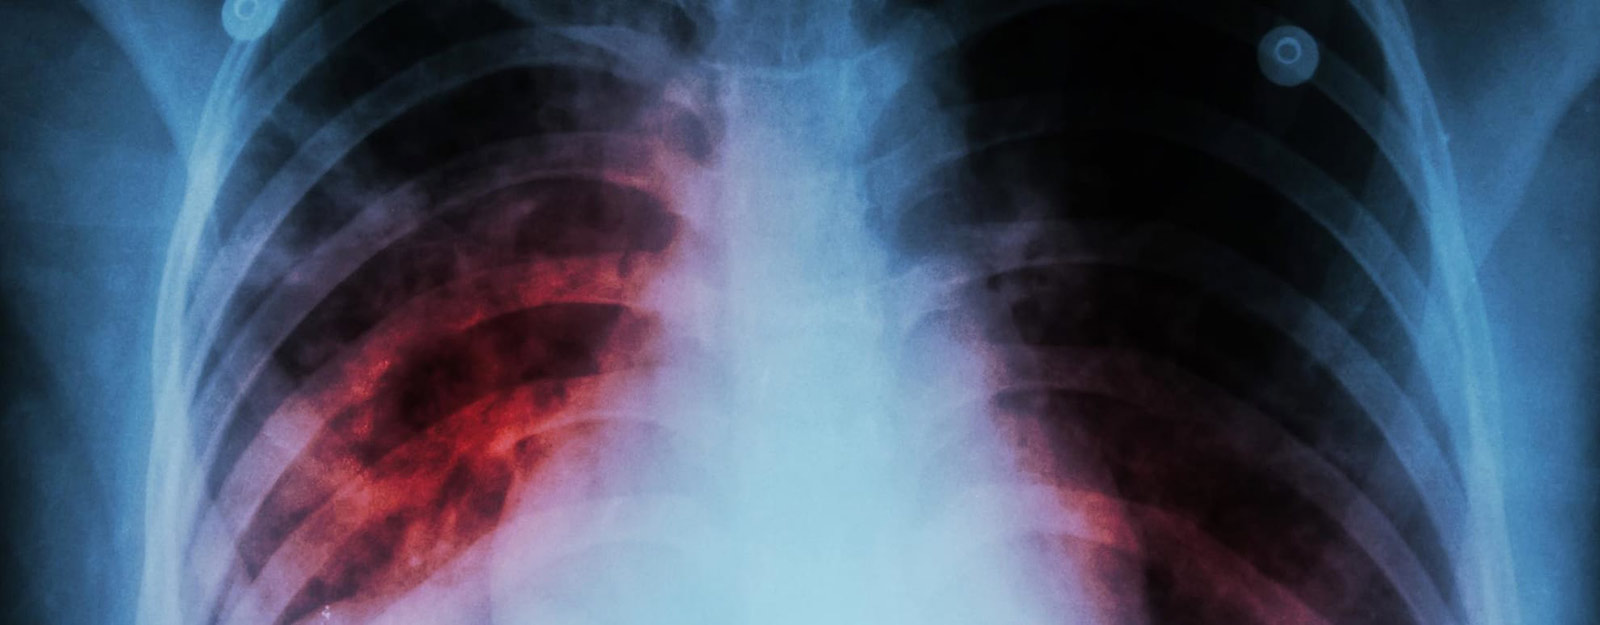

ولفت روبنسون إلى أن إحدى النظريات هي أن السل يسبب كثيراً من الالتهابات في الرئة، وقد يواجه الفيروس صعوبة في إيجاد طريقة للدخول.

وتابع: «ترى رئتاك أنه يوجد بالفعل ما يكفي من البيئة السامة، فتمنع الفيروس».